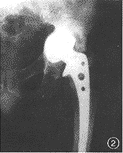

例1男,72岁,右全髋关节置换术后5年出现髋关节疼痛。X线片示右股骨假体内翻下沉,假体远端骨水泥断裂,髋臼假体周围有连续的透亮区。手术中见股骨和髋臼假体周围有大量界膜形成,假体松动(图1)。

图1男,72岁,右全髋关节置换术后5年。右股骨假体内翻下沉,假体远端骨水泥断裂,髋臼假体周围有连续的透亮区图2女,65岁,人工股骨头置换术后5年。髋臼内壁磨损,容积性骨缺损图3女,68岁,右侧人工股骨头置换术。假体外翻位,假体柄自内侧骨皮质穿出图4男,40岁,股骨颈骨折后股骨头缺血性坏死。行人工股骨头置换术,人工股骨头过度前倾位置入图5男,67岁,左侧全髋关节置换术后7年。假体股骨柄断裂,股骨假体近端内翻,骨水泥周围透亮区形成图6男,62岁,左侧全髋关节置换术后4年。髋臼假体金属杯与聚乙烯内衬脱位,髋臼金属假体与股骨假体直接接触